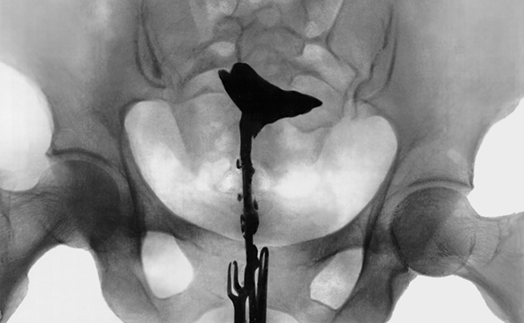

Гистеросальпингография (ГСГ) — это диагностический метод, позволяющий оценить состояние матки и фаллопиевых труб. Исследование проводится с использованием рентгеновских лучей и контрастного вещества для визуализации органов женской репродуктивной системы.

- Делают рентгеновские снимки для оценки распределения контраста.